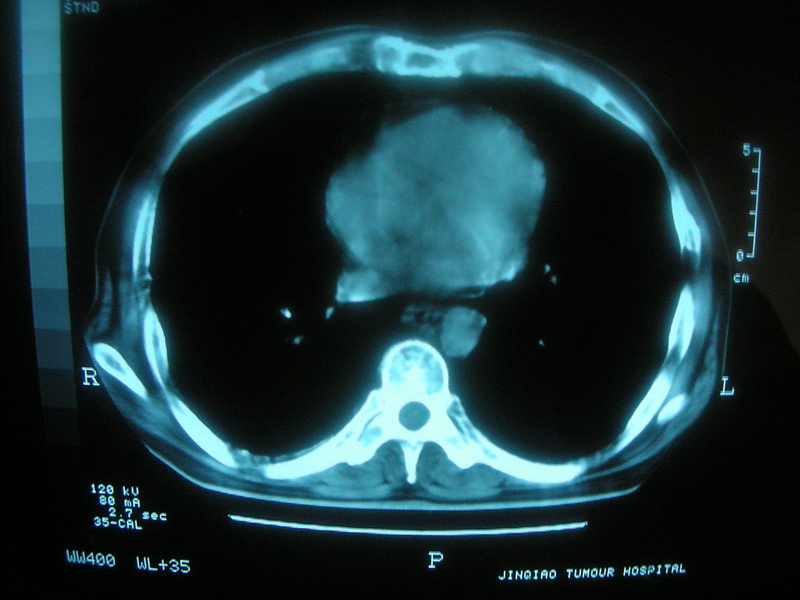

标题: CT11692:男,63岁,糖尿病史15年.抗炎治疗7天,病情 [打印本页]

标题: CT11692:男,63岁,糖尿病史15年.抗炎治疗7天,病情

请老师看看是结核还是炎症?

根据影像表现及临床符合结核感染。

双肺继发性肺结核伴感染!

糖尿病首先考虑结核并感染。